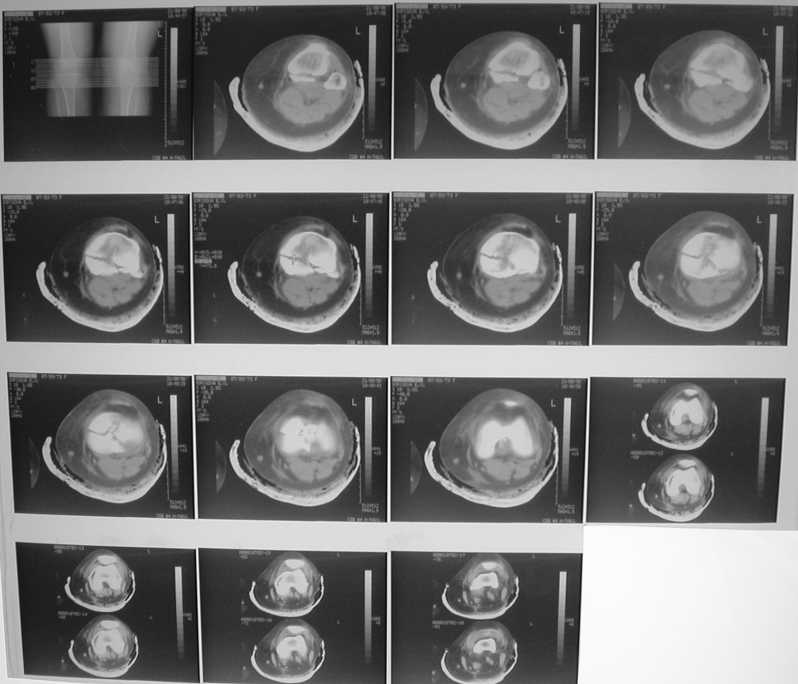

Добрый день всем! Помогите выбрать целесообразный имплантат

Имя     : Борисова1.jpg